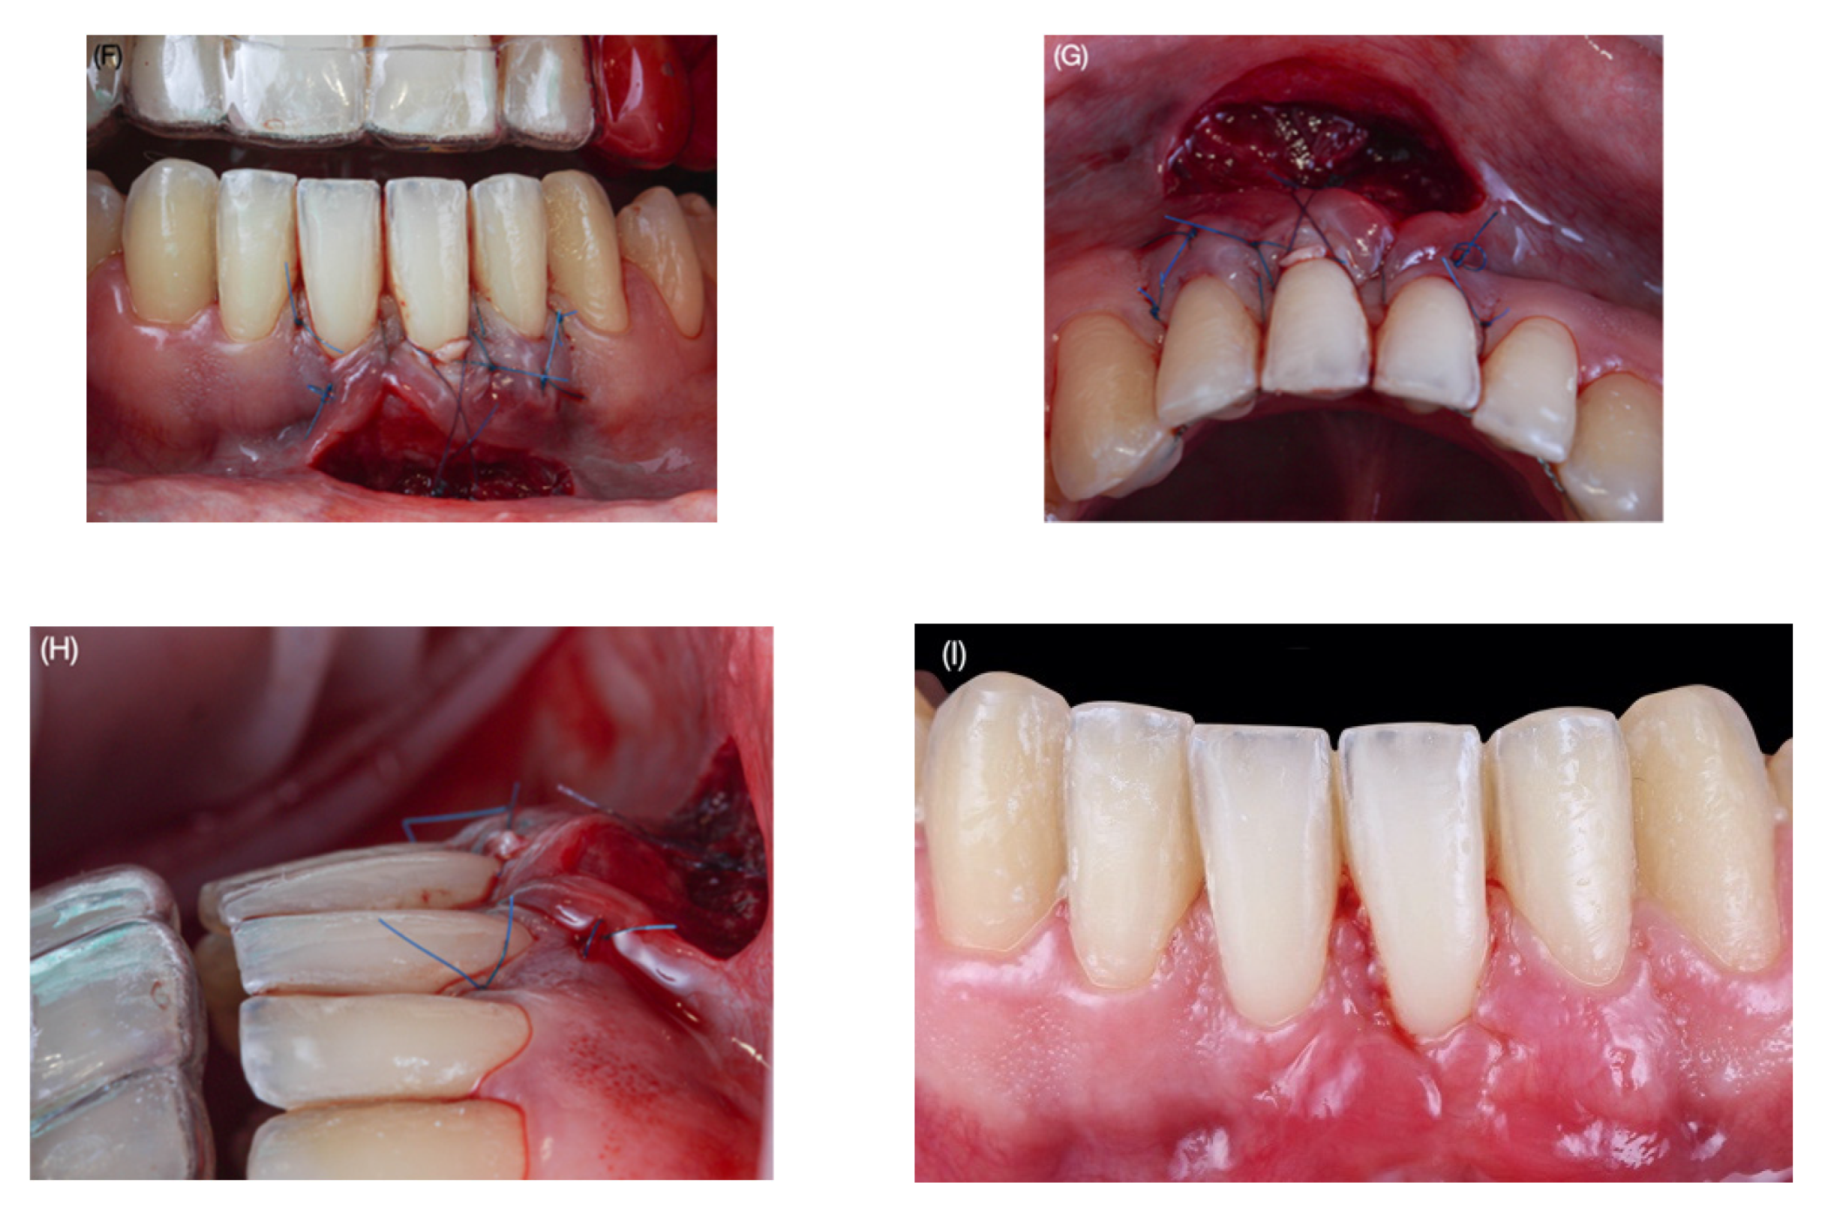

Clinical Outcomes of the Double Lateral Sliding Bridge Flap Technique with Simultaneous Connective Tissue Graft in Sextant V Recessions: Three-Year Follow-Up Study

2.1. Surgical Protocol